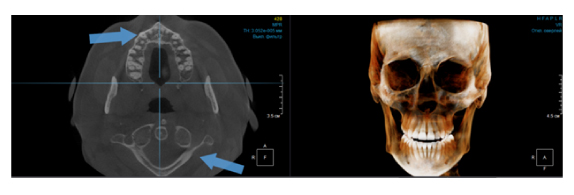

Когда мы отправляем пациента на проведение рентгенологического исследования, то подвергаем его определенному риску. Именно это нужно осознавать, так как в радиологии нет минимально безопасной дозы, поэтому любое назначение должно быть обоснованным. В связи с этим поле обзора является достаточно принципиальным параметром. Если вы врач-терапевт, занимающийся эндодонтией или ортопед, который решил оценить состояние зубов перед протезированием, то вы должны понимать, что проведение исследования с полем обзора 10x10 см будет гораздо информативнее нежели большие снимки (18x16 см и выше). В первую очередь это связано с размером вокселя, о нём я напишу чуть ниже, а второе это то, что вам придется увеличивать изображение по каждому корневому каналу, и от этого вы будете терять в качестве снимка (рис. 1). И ситуация наоборот, если вы ортодонт, то чтобы использовать весь диагностический потенциал, а также возможность загрузить данные для расчёта 3D цефалометрии, то вам нужны снимки, захватывающие весь лицевой отдел черепа. Таким образом, дентальный томограф должен обладать возможностью проведения исследований с разным FOV, обеспечивая нужды всех специалистов. Если ваша клиника базируется на терапевтическом, хирургическом и ортопедическом приёме, то на мой взгляд, можно рассмотреть дентальные томографы с полем обзора 10x10 см или 16x10 см. Последний больше актуален для тех, кто работает с ВНЧС, так как антропометрически в 16 см даже у брахицефалов сустав должен попадать. Если в клинике есть ортодонтическое направление, функциональная стоматология, ЛОР-практика или ЧЛХ, то, безусловно, вышепредставленные снимки не будут отражать всех данных, которые необходимы для диагностики и планирования лечения. Здесь лучше рассмотреть конусно-лучевые компьютерные томографы с зоной сканирования 18x16 или 20x20 см. Особо стоит отметить понятие «сшивки». Есть дентальные томографы, которые делают один цельный снимок размерами, которые описаны выше, а есть аппараты, которым нужно провести две экспозиции и сшить изображения вместе, чтобы получился необходимый объём исследования. Как правило, вторые томографы чуть дешевле, но всё зависит от того, насколько вам нужна максимальная точность исследования. Если при сшивке челюсти и зубы, как правило, совмещаются практически идеально, то на уровне позвоночного столба происходит наслоение тканей и от него уже не избавиться (рис. 2). Второй отрицательный момент – это износ оборудования, логично, что он будет быстрее, так что экономия средств — это ещё спорный вопрос.

Рис. 2. Левый снимок представлен исследованием 20x20 см единым изображением. Стрелками показаны чёткость канально-корневой системы зуба, а также позвоночника. Правый снимок представлен исследованием 16x15 см с функцией сшивки. Стрелками обозначены чёткость зуба, но двойной контур позвоночника.